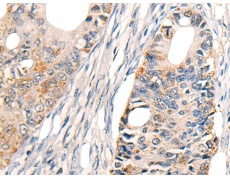

IHC positive control: |

Human ovarian cancer and Human colorectal cancer |

IHC Recommend dilution: |

20-100 |